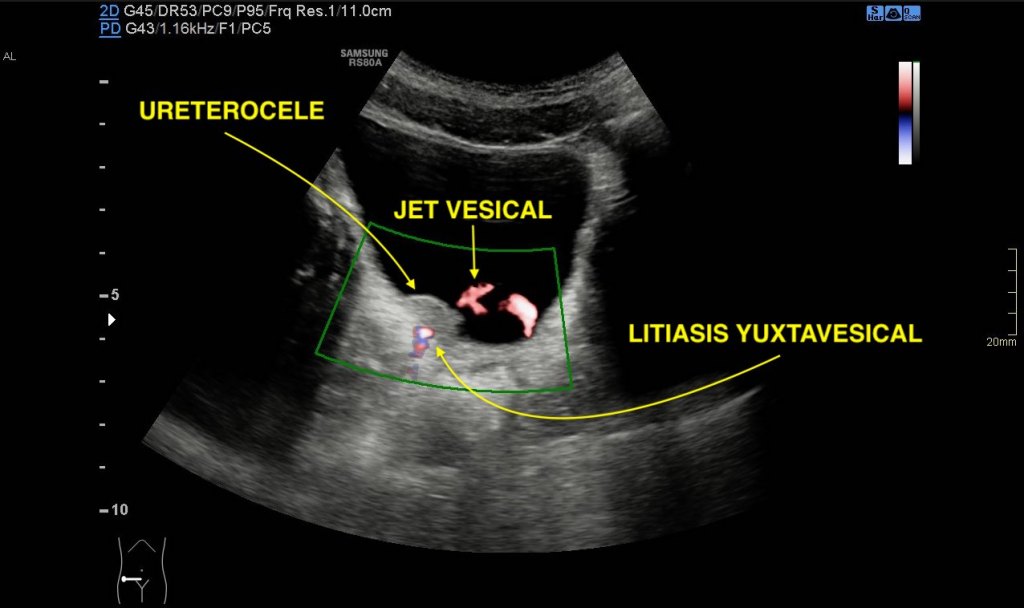

- Ureterocele:

- Un ureterocele es una dilatación en el extremo inferior del uréter, donde se une a la vejiga. En una ecografía, se vería como una estructura quística o un proceso inflamatorio que se interna dentro de la vejiga.

- Puede causar obstrucción del flujo urinario, llevando a ITUs y posiblemente a dolor en el área renal.

- Jet Vesical Conservado:

- A pesar de la presencia de un ureterocele, el jet vesical conservado indica que aún hay un flujo normal de orina desde el uréter a la vejiga. Esto se observaría en una ecografía Doppler como un flujo regular de orina desde el uréter al interior de la vejiga.

- Litiasis Yuxtavesical:

- Se refiere a la presencia de una piedra en la vejiga o cerca de la unión del uréter con la vejiga. Esto podría ser una causa adicional de dolor y ITUs.

- En la ecografía, se observaría como una formación densa, posiblemente con sombra acústica posterior, indicando una piedra.